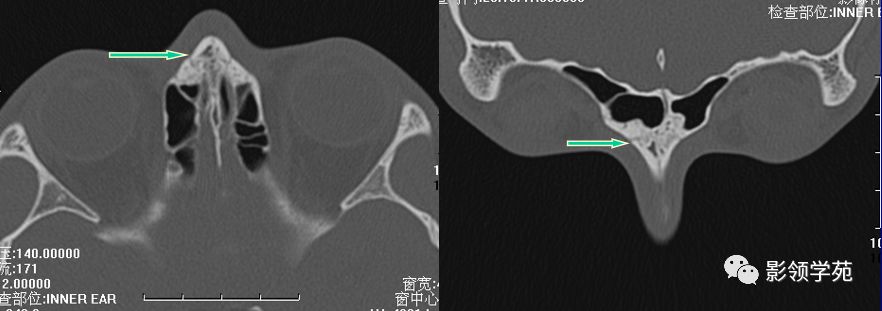

线性骨折 粉碎骨折

右侧鼻骨线形骨折

鼻骨线形骨折

左侧鼻骨线形骨折